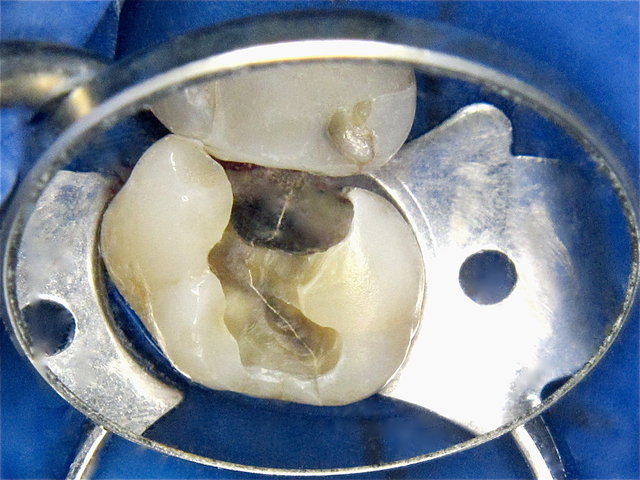

In- und externe Risse nach Amalgam-Entfernung ...

Höckerfrakturen neben Amalgam-Füllung ...

Interner zentraler Riss nach Amalgam-Entfernung ...